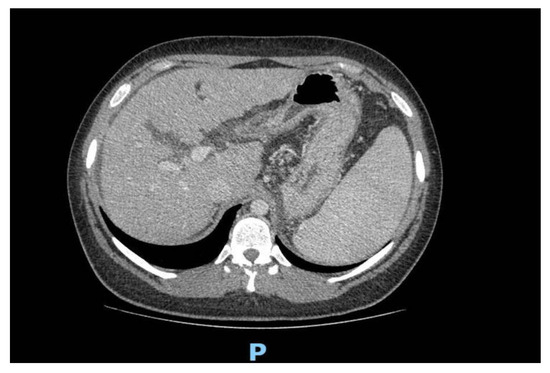

| Abdominal US | Normal liver volume with irregular and cocooned margins and a non-homogeneous echostructure. Hypoechoic nodular formation in the 7th segment of 15 mm. Splenomegaly | Mild hepatic steatosis |